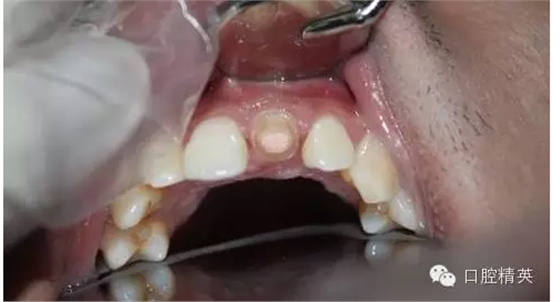

一年輕小伙,在打籃球中,被隊友打斷門牙,來本診所時已經(jīng)露髓,局麻拔髓后,行RCT。后因經(jīng)濟關系,擬鈷鉻樁加鈷鉻烤瓷冠修復,備牙后才留照片:

1:牙根,備牙后,